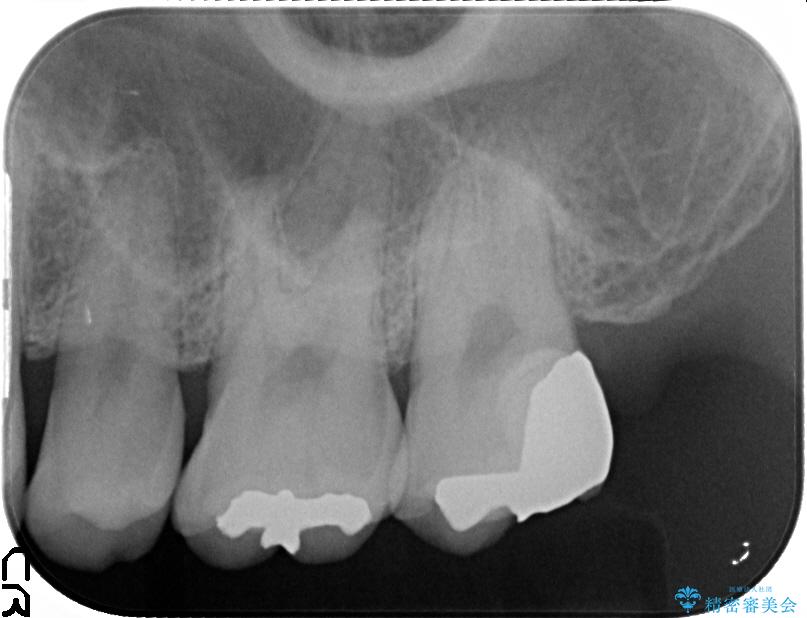

上顎左の一番奥の歯が深い虫歯になって脆くなり、更にその状態に強く噛みしめたわけではない通常の咬合力が加わったことで歯が欠けてしまっていました。

今回は一番奥の歯という位置と、噛み合わせ、清掃状態を加味して適合の高く長持ちするゴールドインレーにて治療することとしました。